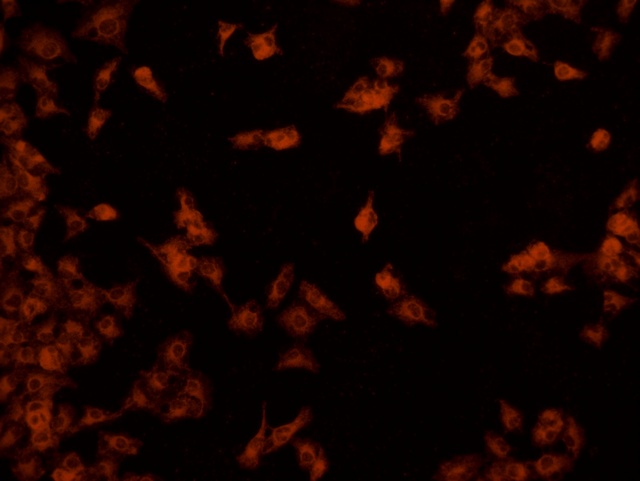

南华大学在生物医学研究领域一直走在学术前沿,近日,该校引进Mshot明美的倒置荧光显微镜MF52-N,搭配显微镜相机MSX2,为细胞切片标本的研究提供了强大的技术支持,进一步提升了科研实力。

MF52-N倒置荧光显微镜以其数显LED荧光模块和深度优化的光路设计,成为细胞切片观察的理想选择。其简单易用的荧光激发操作,大大降低了实验难度,提升了工作效率。同时,该显微镜还能提供高质量的相衬、荧光和明场成像,确保科研人员能够捕捉到细胞切片的每一个细节。

在南华大学的实验室中,科研人员正借助这套先进的显微系统,对细胞切片标本进行深入探索。

此外,MSX2显微镜相机的加入,更是如虎添翼。这款相机以其高分辨率和敏锐的图像捕捉能力,记录了实验过程中的每一个重要瞬间,为数据分析与论文发表提供了有力支持。